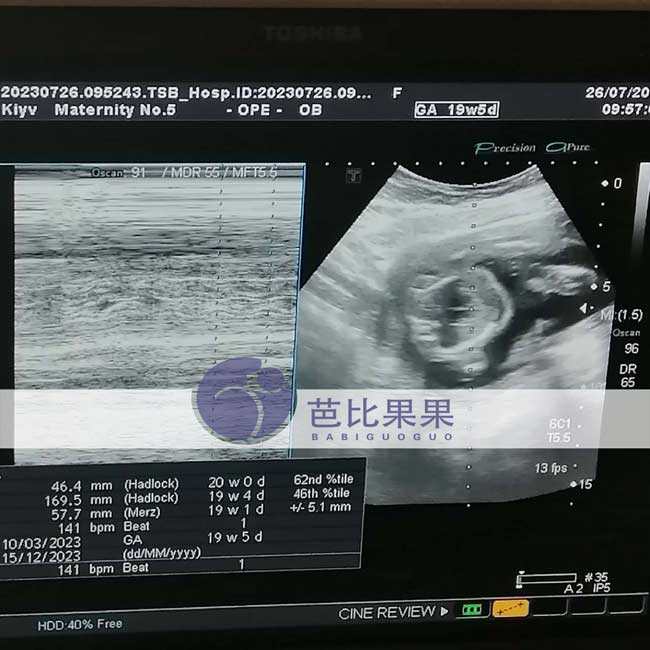

芭比果果三个乌克兰试管助孕家庭的试管妈妈来医院做产检

芭比果果三个乌克兰试管助孕家庭的试管妈妈来医院做产检,其中两位做B超检查,一位常规孕检,妈妈们都顺利通过了检查。